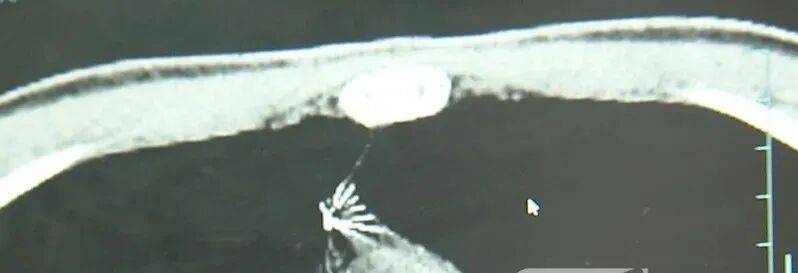

进一步的CT检查确认,异物是一枚金属针,斜插在肺组织内,位置十分凶险。

杭州市第一人民医院心胸外科副主任冯兴说:“我们看到这个针的尖锐部,正好指向他体内的一个大血管,边上是上腔静脉和胸主动脉,因此这个针稍有不慎,就有可能造成周边血管的损伤,甚至危及生命。”